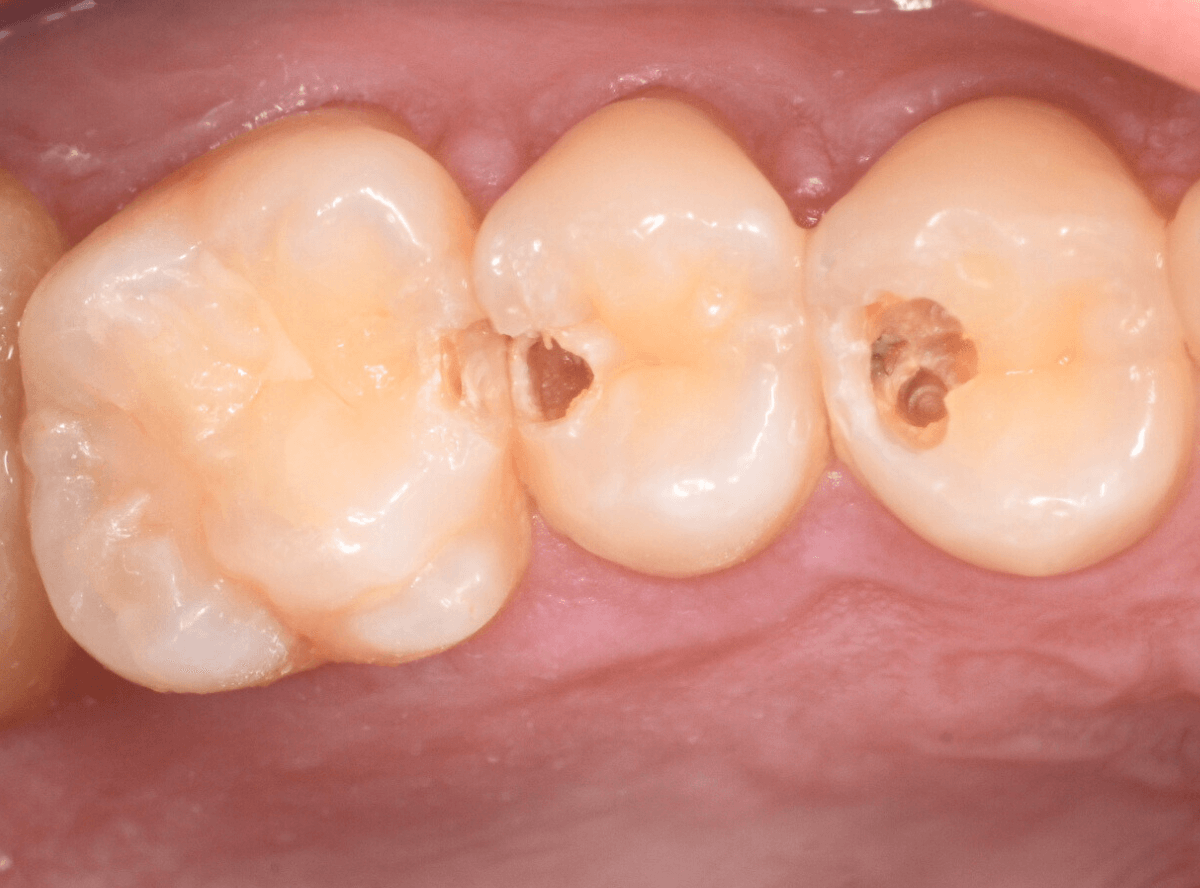

Case.22 痛みはないけど、歯のすきまから大きな虫歯

上の小臼歯の間が虫歯になっていた患者さんです。

症状はありませんし、見た目からも虫歯があるかはわかりませんでした。

治療を開始します。

少し削ると、中からすぐに虫歯が出てきました。

ある程度、虫歯を除去したところで、う蝕検知液で確認します。

赤く染まっている部分が虫歯です。

まだまだ虫歯が中で残っている状況で、かなり深い虫歯なのが確認できます。